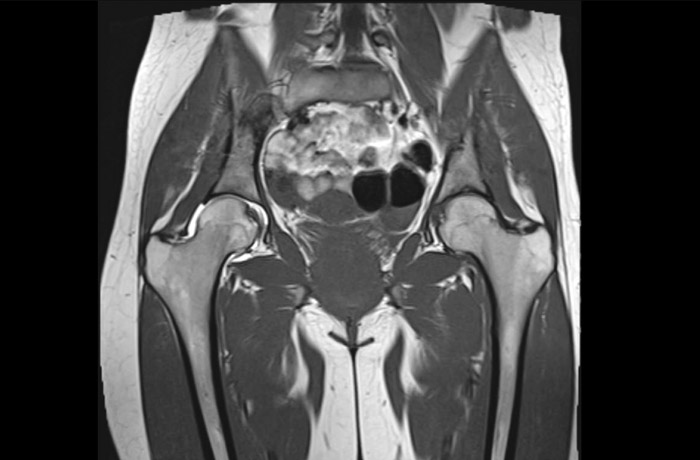

МРТ тазобедренного сустава проводится для получения снимков с послойным изображением структур исследуемой зоны. В результате процедуры сканированию подвергается не только сустав, но и все близко расположенные ткани. Диагностика применяется для выявления патологических процессов в тазобедренном суставе, как в степени прогрессивности, так и на начальной стадии, когда отсутствует внешняя симптоматика.

Показания для МРТ суставов в области тазобедренной кости:

1. ревматические поражения;

2. артриты инфекционного типа;

3. постоянные болевые ощущения;

4. асептический некроз головки бедра;

5. ущемление нервов или сухожилий.